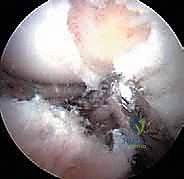

الخطوة 3: الاستكشاف بكاميرا 4K

يتم إدخال منظار مزود بكاميرا عالية الدقة (4K) وإضاءة قوية. تُعرض الصورة مكبرة على شاشة أمام الجراح، مما يسمح له برؤية أدق تفاصيل الغضروف والشفا الحقي بوضوح يفوق الرؤية بالعين المجردة.

الخطوة 4: معالجة الانحشار ونحت العظام (Osteochondroplasty)

باستخدام أدوات دقيقة وصغيرة جداً (مثل المبرد الآلي)، يقوم الدكتور هطيف بإزالة النتوءات العظمية الزائدة.

الخطوة 5: إصلاح الشفا الحقي (Labral Repair)

إذا كان الشفا الحقي ممزقاً (وهو أمر شائع جداً)، لا يتم استئصاله، بل يحرص الدكتور هطيف على إصلاحه للحفاظ على وظيفة المفصل. يتم ذلك باستخدام "خطاطيف خياطة" (Suture Anchors) صغيرة جداً تُزرع في العظم وتُستخدم لربط وخياطة الشفا وإعادته لمكانه الطبيعي.